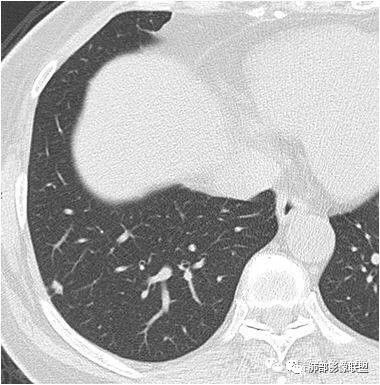

病例一:

正常情况下,肺内淋巴结是不显示的,一般是慢性炎症所致,老年人和吸烟者多见。影像上常见于胸膜或叶间胸膜下,迄今为止,所有的报道均距胸膜或叶间胸膜小于2.0cm以内。也可以表现为与胸膜或叶间胸膜相贴的结节。绝大多数位于中下叶(气管隆突水平以下),上叶也可见到,但较少见。

长径均小于12mm。典型的形状为三角形,也可以为梭形、圆形或椭圆形。诊断的关键在于见到1-5条细线与胸膜、叶间胸膜或静脉相连,有时状如坐落于电路板的“二极管”,但以薄层CT显示为佳。有作者病理对照线状影为小叶间隔,有作者病理对照为淋巴管。其实不矛盾,因为淋巴管走行于小叶间隔内。